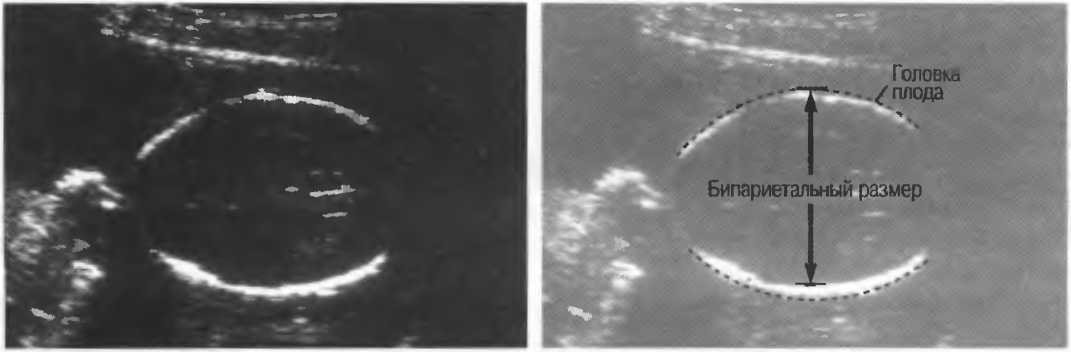

Рис. 13г. Головка плода. Слева: общая чувствительность слишком высока. Справа: общая чувствительность определена правильно, однако она слишком высока для точного измерения бипариетального диаметра.

Рис. 13д. Общая чувствительность слишком низка для исследования внутренней зхоструктуры, но достаточна для точного измерения бипариетального диаметра.

Рис.13е. Слева: плохая визуализация в результате слишком высокого усиления передних отделов; сравните нечеткое изображение передней части головки с достаточно четким изображением задних отделов (сравните рис. 13ги 13д;. Справа: регулировка по глубине была изменена; теперь определяется слишком низкое усиление близких структур и слишком высокое усиление глубокорасположенных структур.